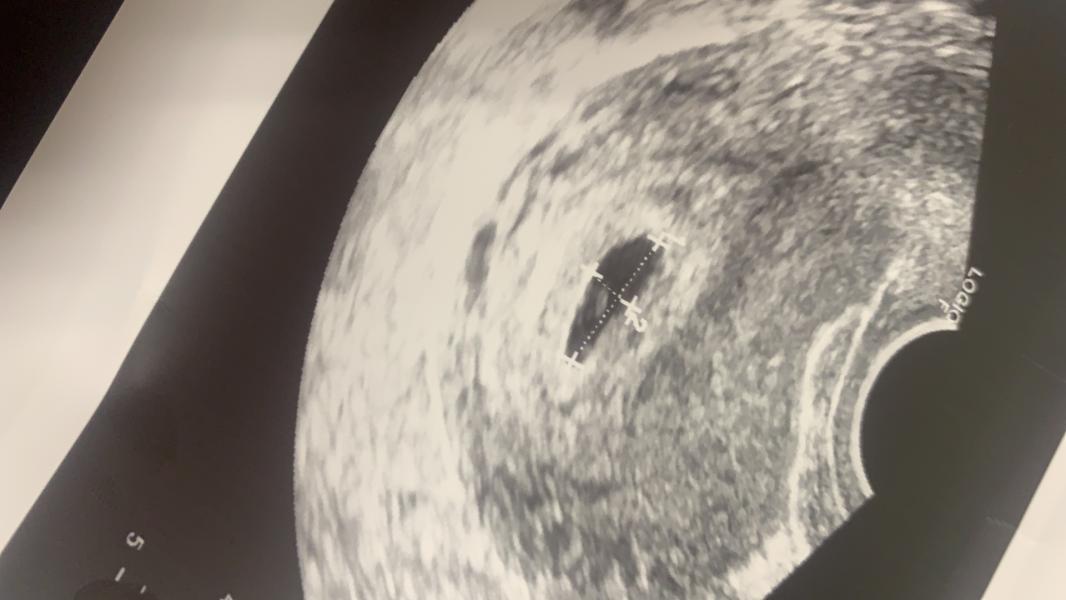

Подскажите , может кто знает сбоку от жм точка это не эмбрион ещё ?

@larisa7778, ну потому что его не четко видно, но он определенно есть. На бОльшем сроке будет уже четко видно)

Все видно! УЗИ аппарат не очень. И уже ж м есть! Просто эмбриончик маленький и на таком аппарате видимо решили его не измерять...